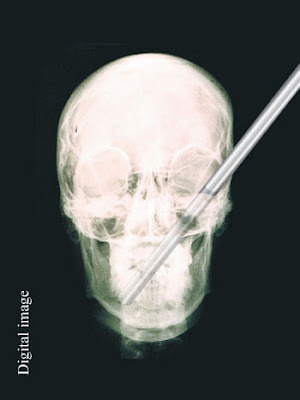

3. Terhunus dalam tengkorak

Michael Hill dari Jacksonville Florida ditikam di kepalanya dengan 7-inci pisau oleh orang tak dikenal yang muncul di depan pintu, 2007 lalu. Dia saat ini memegang Guinness World Records, Judul: "Objek Terbesar yang dikeluarkan dari tengkorak manusia."